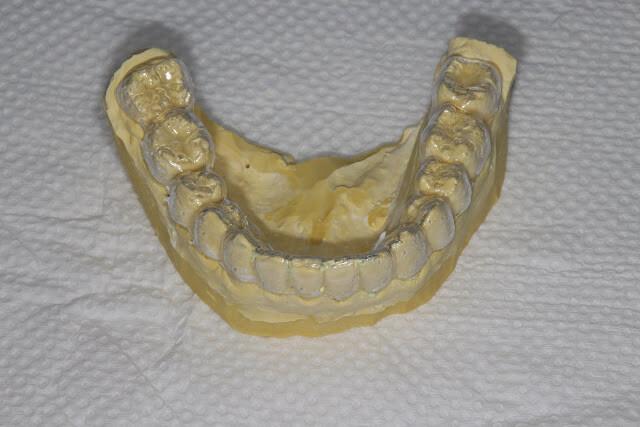

透明維持器(clear overlay)在石膏模型上製作時的樣子

透明維持器(clear overlay)與石膏模型分離,跟隱形牙套很像吧,兩者工序很像,只是材質不同